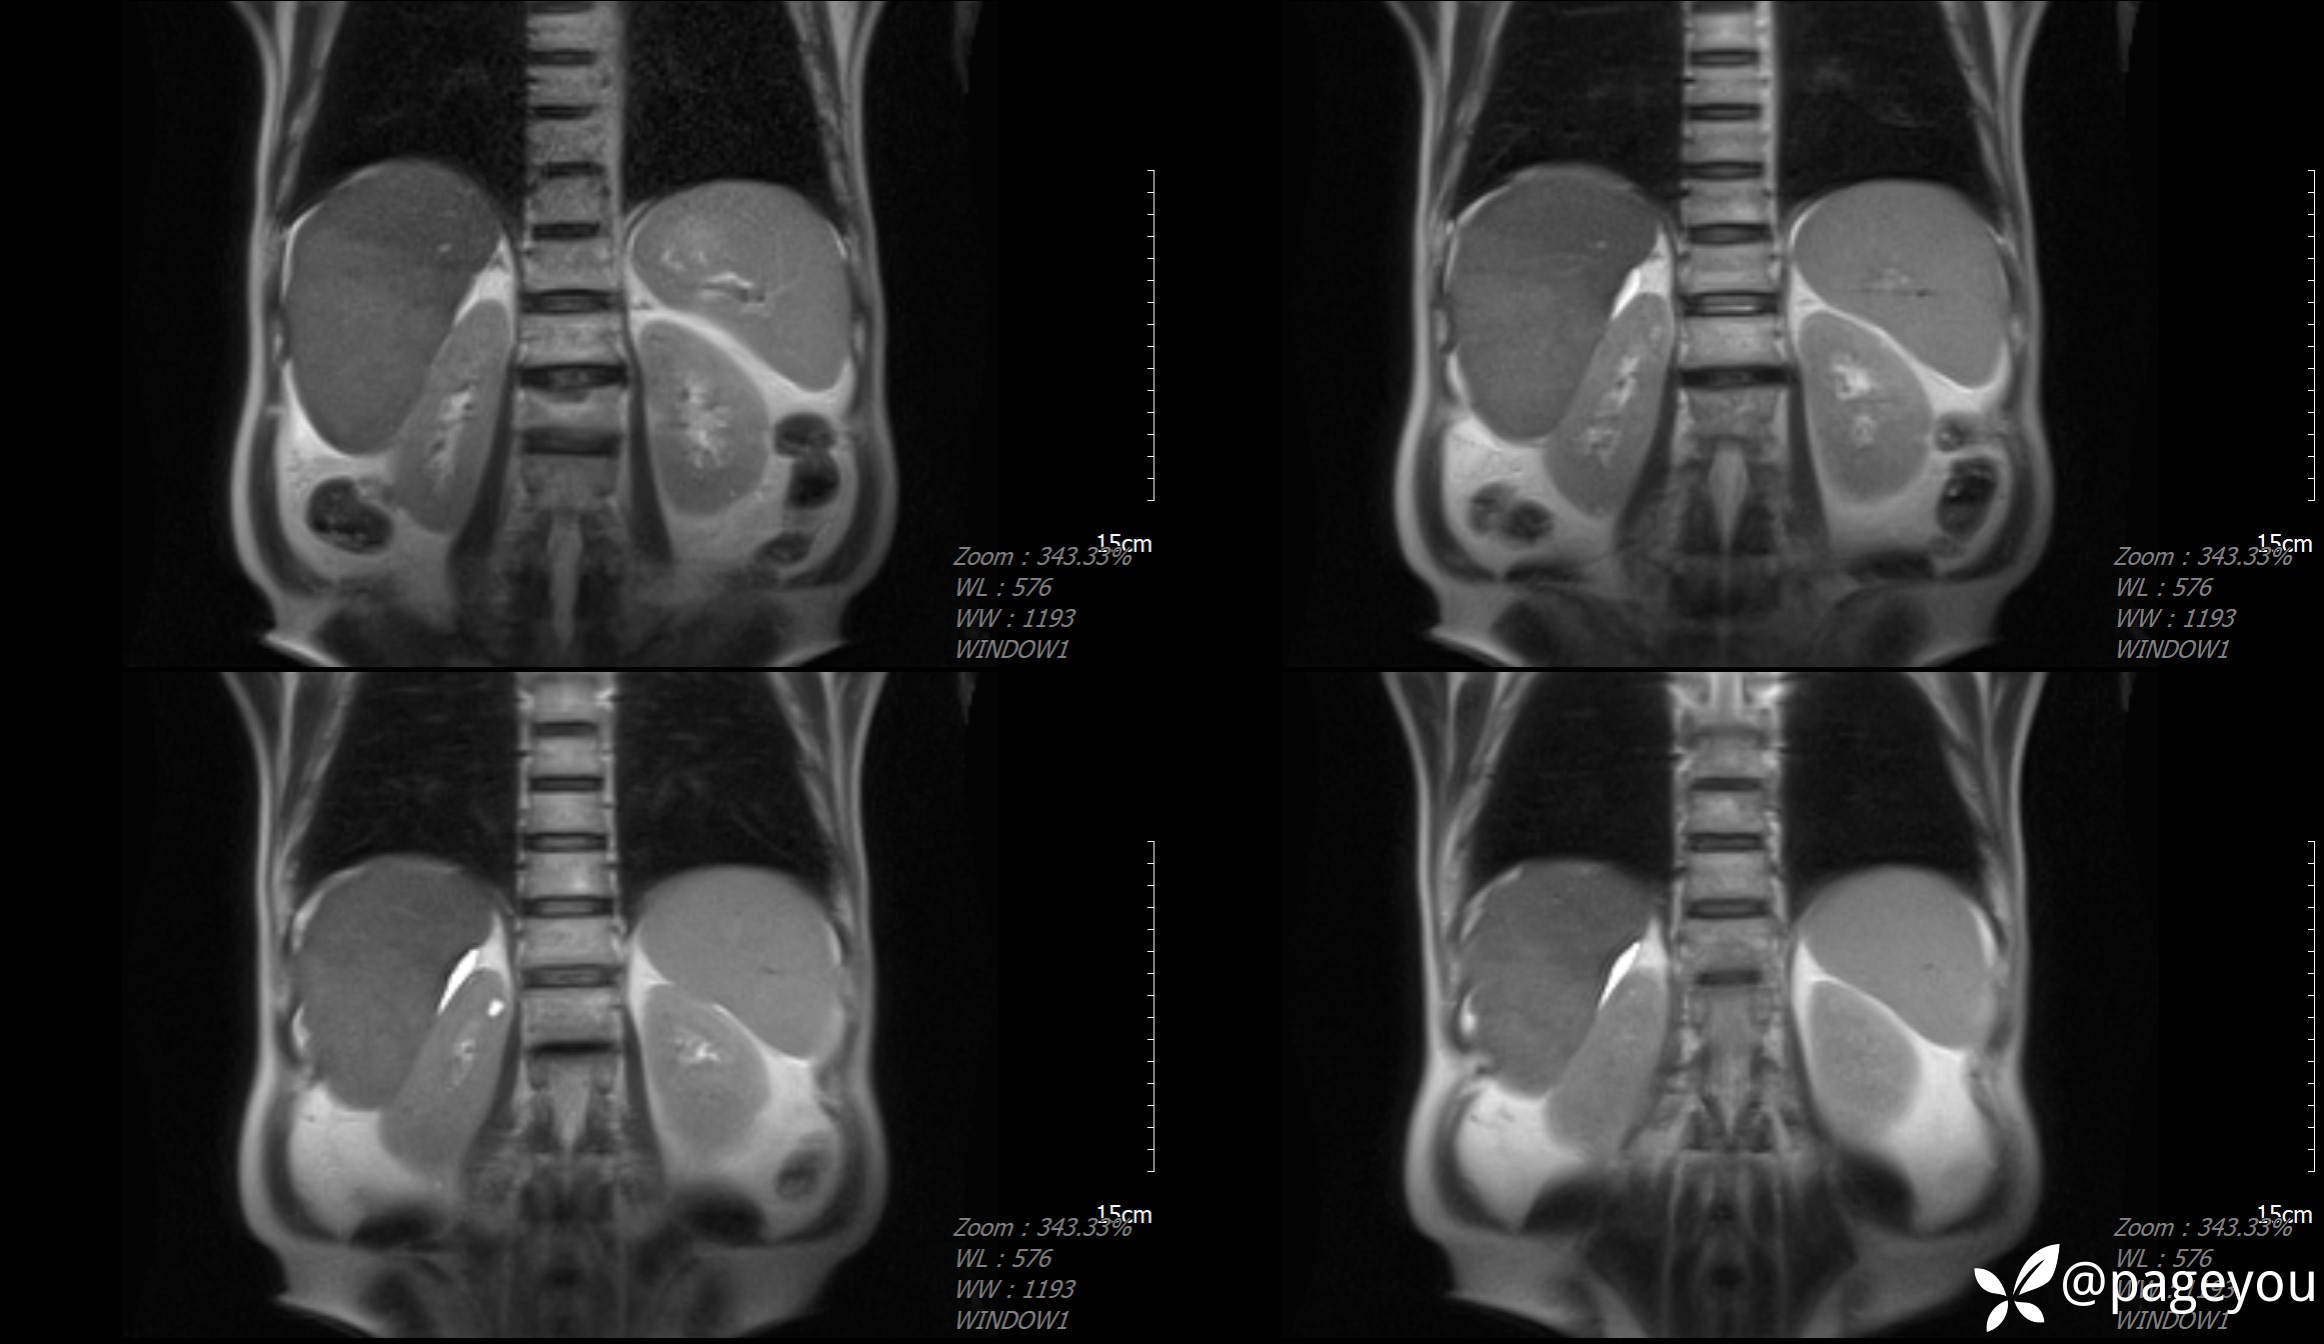

MRI检查: